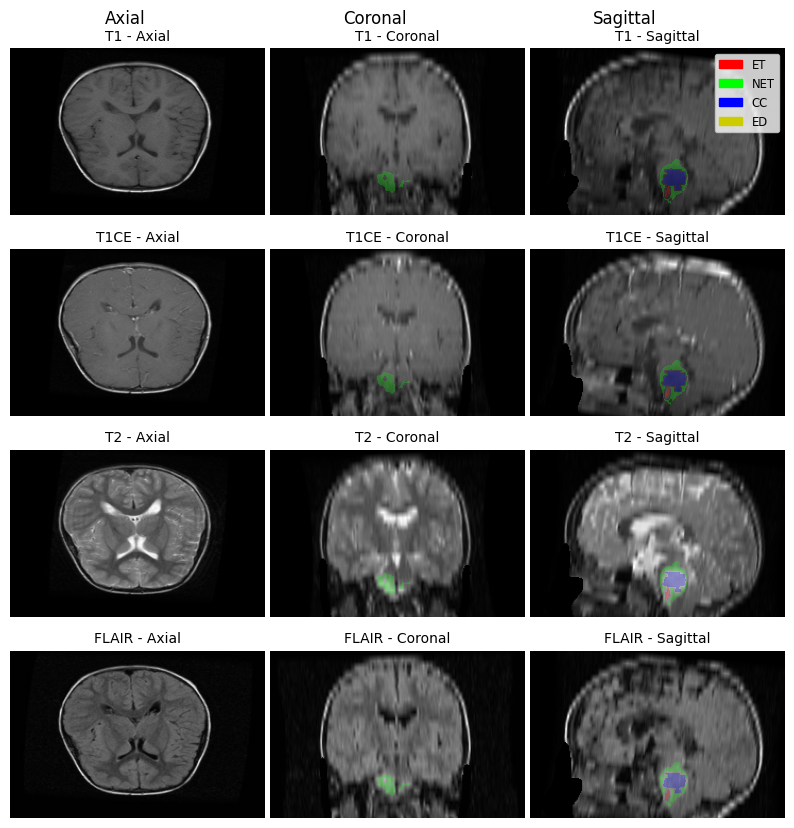

BraTS PED The BraTS-PED dataset [9] consists of multi-institutional conventional and structural MRI scans from 464 pediatric cases of high-grade glioma. There is heterogeneity in the images’ quality due to the different protocols and equipment used. The data went through several preprocessing steps to ensure data integrity and patient anonymity. This year’s task evaluates the accuracy of segmenting the tumor into six sub-regions of interest: the enhancing tumor (ET); the tumor core (TC); the whole tumor (WT); the non-enhancing tumor core (NETC); the cystic component (CC); and the peritumoral edema (ED). Out of these regions, only the first 3 are predicted by the model, and the latter 3 are inferred at testing time by the BraTS organizers. A sample from the dataset is shown in Figure 2. A preliminary automated segmentation pipeline was used to obtain the segmentation labels, and the results were then manually refined by volunteer neuroradiologists. These refinements underwent iterative reviews and approvals by three board-certified neuroradiologists until the labels met the criteria for public release [9].

Refer to caption

Figure 2: Different cross sections of the four modalities obtained from a sample data-point from the provided dataset for pediatrics challenge along with the corresponding segmentation masks